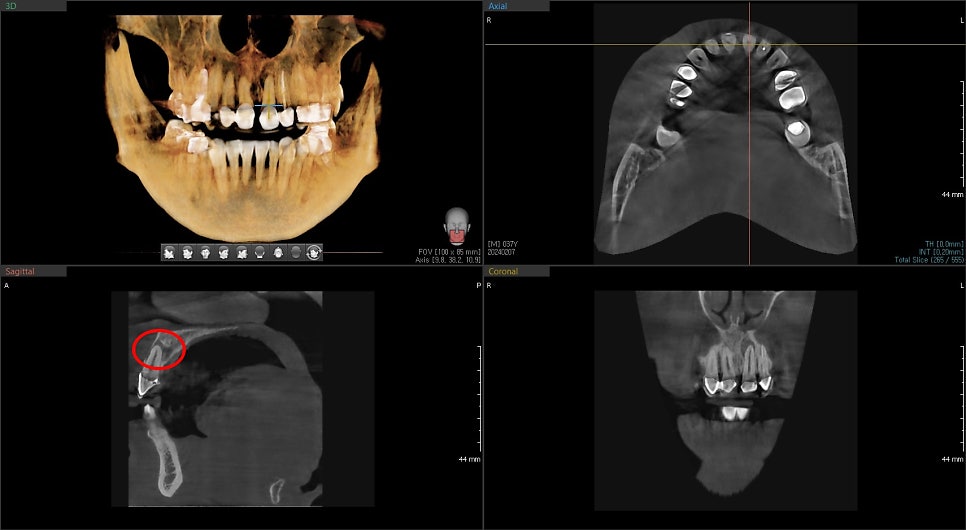

염증이 생긴 곳의 위치가 일반적이지 않아 CT를 찍어보았습니다.

흔들리지는 않지만 뿌리 주변 뼈가 염증반응으로 인해

많이 소실되어 보입니다.

일반적으로 치아 신경에서 온 염증으로 인한 뼈의 소실은

신경치료 후 치유가 되면 다시 건강한 뼈가 채워주게 됩니다.